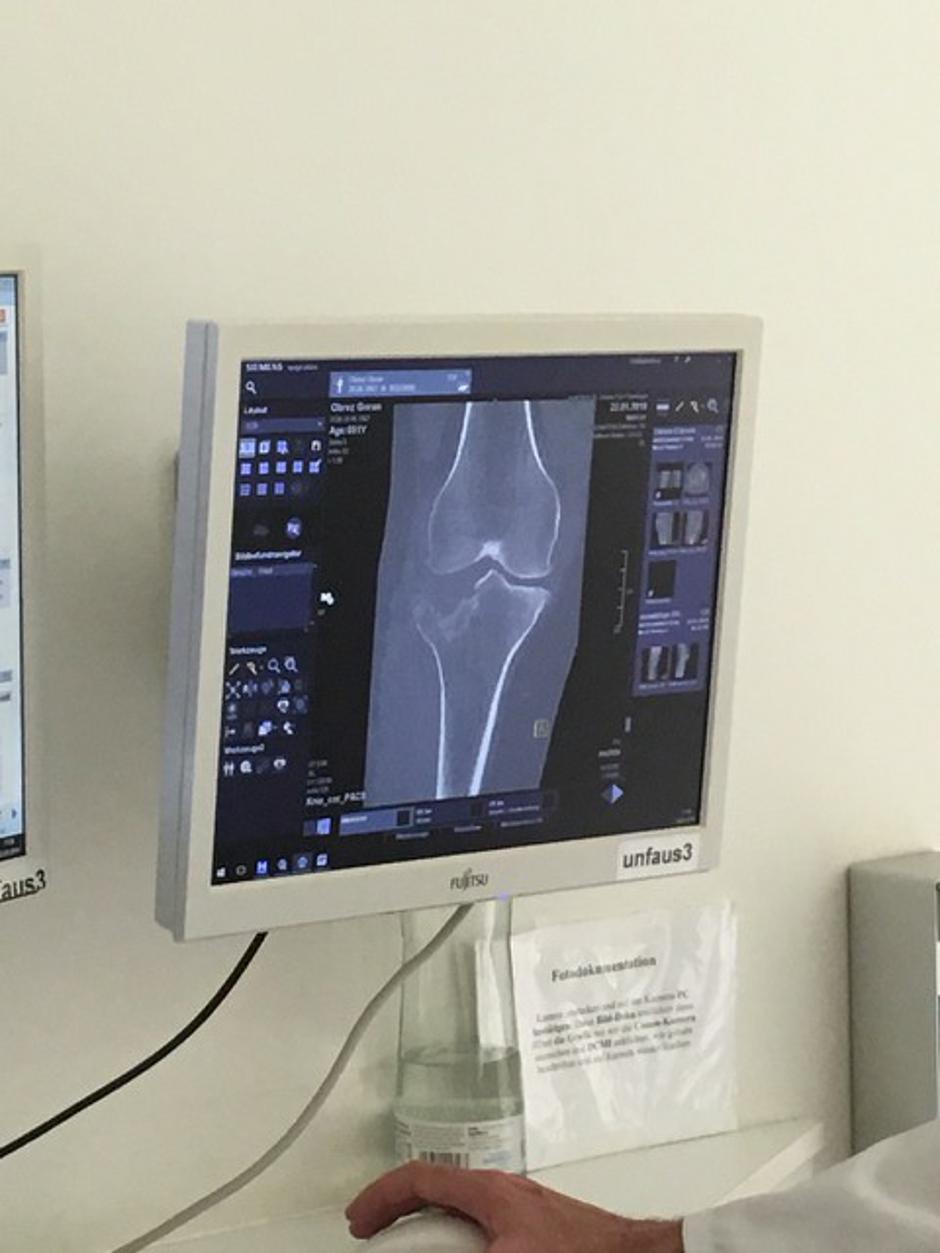

O razsežnosti poškodbe priča rentgenski posnetek.

Poškodba kolena je vse prej kot nedolžna, česar se Obrez zelo dobro zaveda. "Zdravniki so mi povedali, da je hudo. Seveda je hudo, če mi je odbilo polovico kolena," je nazorno dejal.

Kako hudo je dejansko stanje, je razvidno z rentgenskega posnetka, ki ga je posebej za zurnal24.si posredoval sloviti televizijski komentator.